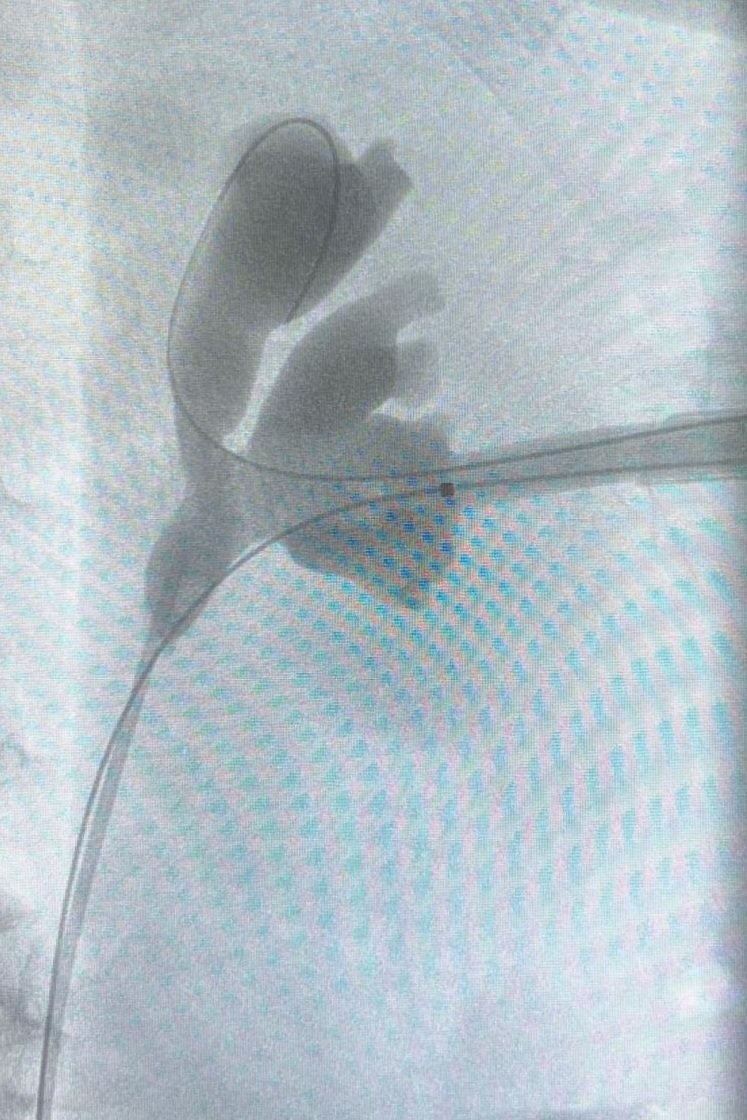

🎯 Proud of sharing our experience in the access to the upper calyx in supine position 📄 Published in Urolithiasis https://t.co/9NVHpYJ9V0 👀 Have a look at our technique & 📊 results in the first 100 cases Thanks to my team for the effort! #PCNL

#uppercalyx

#teamwork

9

18

80

Advanced supine #PCNL workshop at #HURH with @CoralManso US & fluoroscopy Complex cases #miniECIRS

#uppercalyx Thanks to @bsc_urology for the support #lithovueElite Proud of my team! @kikegonzalez11 @PaulaMaple

3

7

22

#uppercalyx Thanks to @bsc_urology for the support Proud of my team! @kikegonzalez11 @MariaJoseLnza

2

5

23

Honored to be part of the live surgery session at #EAU25

#MiniECIRS with @CoralManso & @duque_dra in elderly patient Semi-live #Miniperc to the upper calyx in #supine Grateful to @ROC_Urologia for the hospitality, we felt at home, and @AlbertoBreda1 @Uroweb for the invitation

8

44